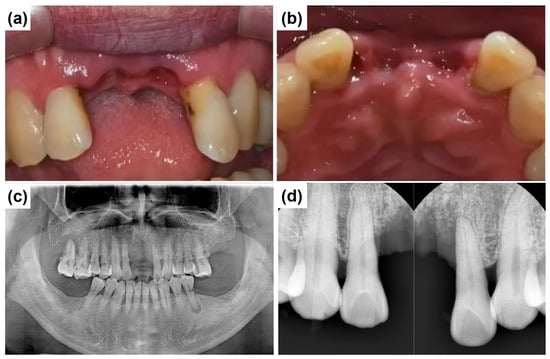

A 58-year-old male patient reported to Mir Dental Hospital at Daegu with missing maxillary central incisors (teeth #11 and #21). The patient was a heavy smoker but had no significant systemic conditions. He revealed that he had lost the teeth three months prior due to periodontal disease. Intraoral examination confirmed the absence of teeth #11 and #21. Figure 2a,b illustrate the clinical presentation at the initial visit, demonstrating severe alveolar ridge resorption and distinct U-shaped gingival recession. Radiographic evaluations, including cone-beam computed tomography (CBCT) and clinical examinations, were conducted to assess bone loss and optimize treatment planning. A panoramic radiograph revealed generalized poor periodontal health (Figure 2c), with notable horizontal alveolar bone loss and vertical bone defects in the edentulous region. Significant labial alveolar bone loss was observed, especially mesially around tooth #22 (Figure 2d).

Figure 2.

Preoperative clinical and radiographic evaluation. (a) Labial intraoral view of the anterior edentulous region (at the initial visit) shows the absence of maxillary central incisors (#11 and #21) and significant alveolar ridge resorption. (b) Occlusal intraoral view of the maxillary anterior ridge, severe horizontal ridge atrophy. (c) Initial panoramic radiograph shows the overall periodontal condition and alveolar bone status. (d) Preoperative intraoral periapical radiograph of the maxillary anterior region illustrates alveolar bone loss and root morphology before implant placement.